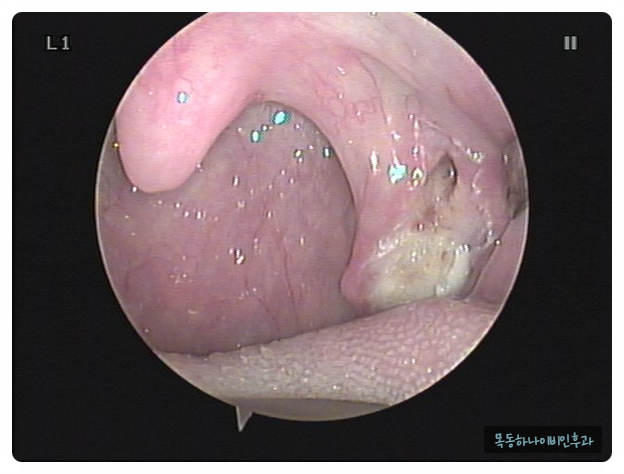

편도결석은 편도선 안에 있는 얇고 깊은 홈에 음식물 찌꺼기나 각종 분비물이 침착하여 돌처럼 단단해진 물질입니다. 크기는 눈곱처럼 작기도 하지만 손톱 크기 정도의 큰 결석이 나오기도 합니다. 색깔도 다양하고 흰색에서 노란색이나 치즈색을 보이기도 합니다. 건강한 성인에서도 약 10%에서 편도결석이 관찰됩니다. 물론 편도 결석이 있습니다만, 결석이 있다는 것을 알지 못하는 분도 많습니다.

편도결석은 눈으로 확인하시면 바로 진단이 가능합니다. 양치질과 기침을 하다가 튀어 나오거나 눈에 보이는 경우도 종종 있습니다. 증상은 있지만, 눈으로 관찰할 수 없을 때 병원에서 후두 내시경으로 목구멍 안쪽에서 관찰될 수도 있습니다.